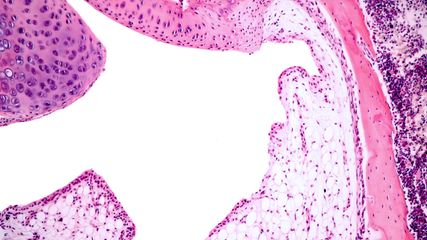

Im Januar 2024 ist die neue Leitlinie zur Behandlung der Lupusnephritis von KDIGO (Kidney Disease: Improving Global Outcomes) herausgekommen. Prof. Britta George erklärt, wann man die neu hinzugekommenen Präparate Belimumab und Voclosporin einsetzt.

B. George: Die aktive proliferative Lupusnephritis (Klasse III/IV) ist eine aggressive Erkrankung, die zügig und suffizient therapiert werden muss. Auf eine Triple-Therapie sprechen mehr Patienten an als auf SOC alleine.2–5 Ob aber alle Patienten eine zusätzliche Therapie mit Voclosporin oder Belimumab benötigen, ist noch unklar. Bislang gibt es hierfür keine validierten Kriterien. Dadurch, dass in den Leitlinien parallel weiterhin der SOC empfohlen ist, bleibt dem behandelnden Arzt ein grosser Entscheidungsspielraum, ob er eines der beiden neuen Medikamente additiv einsetzt. Die Entscheidung sollte unabhängig von ökonomischen Überlegungen getroffen werden. Chronizitäts- oder Aktivitätszeichen in der Biopsie können bei der Entscheidung helfen. Eine Erweiterung der Therapie könnte auch denjenigen Patienten helfen, die aufgrund von Nebenwirkungen die empfohlene MPAA-Dosis nicht erreichen.